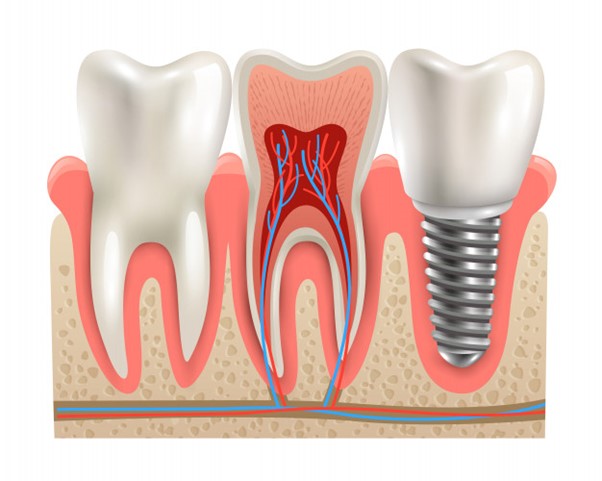

Dantys yra svarbūs kiekvienam žmogui. Neturint vieno ar kelių dantų gali kilti nemažai nepatogumų. Jei žmogus neturi dantų, tuomet jam yra sunkiau valgyti, kalbėti. Dėl šios priežasties dantų protezavimas yra dažnai pasirenkama paslauga. Protezavimo metu yra įstatomas netikras dantis, kuris nesiskiria nuo kitų. Jei žmonės nežinos, jog turite vietoje danties protezą, jie tikrai to nepastebės. Dantų protezavimo prireikia neretai. Pasitaiko, jog net ir jauniems žmonėms reikia šios paslaugos. Turbūt dažniau dantys krenta vyresniems žmonėms, tačiau jaunimas irgi gali neturėti dantų. Odontologų paslaugos yra nebrangios, tačiau žmonės vis tiek nori sutaupyti, todėl nesilanko pas odontologus reguliariai. Dėl to dantys genda, gedimai po kurio laiko tampa rimti ir dantis iškrenta. Tokiu atveju reikia įstatyti kitą. Dantys gali kristi ir dėl kitų priežasčių. Pasitaiko, jog dantis iškrenta, kadangi žmogus susimuša, neatsargiai valgo kietą maistą ir panašiai. Gali įvykti įvairių įvykių, kurių metu iškrenta dantis. Norint to išvengti, svarbu juos prižiūrėti ir atsargiai elgtis. Nutikus taip, jog dantis iškrenta, reikia rasti odontologą, kuris galėtų įstatyti naują dantį. Dantų protezavimas kainuoja brangiai. Jei reikės vieno danties, tuomet mokėti reikės apie 700 – 1 000 eurų. Prireikus daugiau nei kelių dantų, kaina bus gerokai brangesnė. Dantų protezavimas yra brangi paslauga, todėl svarbu prižiūrėti dantis, jog nereikėtų jos pasirinkti. Svarbu valyti dantis po kiekvieno valgio, atlikti burnos higieną, taisyti dantis vos tik atsiradus gedimui. Tokiu atveju dantys bus sveiki ir nereikės galvoti apie dantų protezavimą. Dantis prižiūrėti turi kiekvienas žmogus, kuris nori, jog jie būtų sveiki.

Dantų protezavimas yra brangi paslauga. Pasitaiko, jog reikia atstatyti visą žandikaulį, tuomet mokėti gali reikėti 3 000 – 8 000 eurų. Kaina yra brangi, todėl dantis prižiūrėti yra svarbu. Tačiau, jei dantys buvo neprižiūrimi, tuomet nebūtina iš karto pasirinkti brangias paslaugas. Sutaupyti reikiamą sumą gali būti nelengva, todėl naudinga pasirinkti pigesnį variantą ir tik po kurio laiko rinktis dantų protezavimą. Dažnai žmonės pasirenka išimamus protezus, nes jie pigesni, tačiau po kurio laiko sutaupo ir renkasi neišimamus protezus. Jie patogesni, nes neiškrenta ir nereikia jų išimti. Dantų protezavimas yra brangi paslauga, todėl kartais naudinga rasti būdų kaip sutaupyti. Pasidomėkite kainomis ir pasirinkite odontologijos centrą, kuris pasiūlys pigesnes kainas, tuomet galėsite sutaupyti.